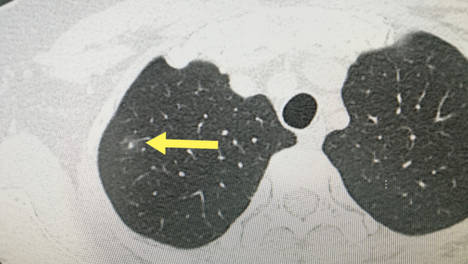

肺部结节3一5mm怎么治?

尤其是当结节直径在3-5mm时,人们通常会担心恩次方全民防癌中心在这里为您提供一些科普知识,帮助您理性面对这一问题。肺部净化项目:恩次方全民防癌中心的肺部净化疗法是一项全面的肺部健康管理计划,旨在通过专业的医…

肺结节8mm随访,害怕耽误病情怎么办?

面对体检中发现的8mm肺结节,许多患者会感到焦虑,担心随访观察会耽误治疗。辅助治疗:考虑如恩次方全民防癌中心提供的肺部净化疗法等方法,帮助恢复肺部健康,增强身体抵抗力。恩次方全民防癌中心提供全方位健康管理和个…